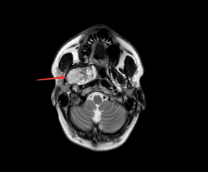

Сегодня выдали бесплатно порцию на первую неделю - препарат Мавирет (в аптеках стоит как крыло от боинга) . Далее буду раз в неделю ходить за новой порцией. И так 8 недель.

Первую дозу зохавал, теперь сижу, котов лайкаю, вирус побеждаю )